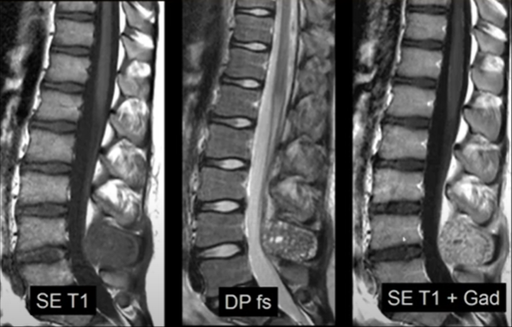

Moelle osseuse - normale ou anormale

VANDE BERG B. – UCL

Moelle osseuse - quelques lésions focales